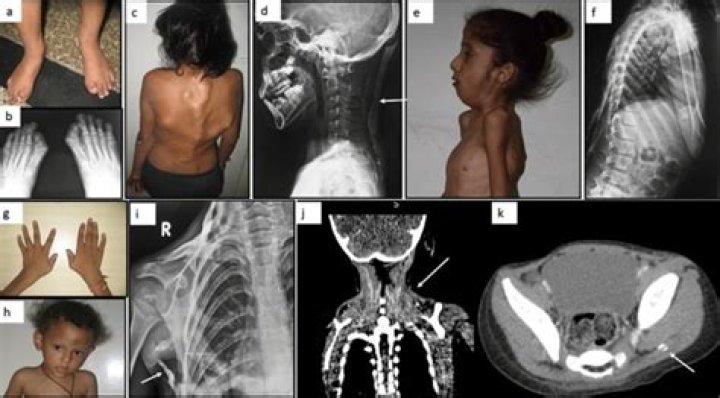

Stone Man syndrome or fibrodysplasia ossificans progressiva (FOP) is an extremely rare (1 in 2 million) genetic disorder characterised by ectopic ossification of the skeletal and connective tissues leading to progressive fusion of axial and appendicular skeleton.

Genetic transmission is autosomal dominant with variable expression but the inheritance because of spontaneous mutations is most common. FOP is characterised by the cardinal features of heterotopic progressive osteogenesis and digital anomalies.

What are signs of Stone Man Syndrome? The only known sign of significance that assists with the early diagnosis of this condition is the presence of a congenitally deformed great toe. Plain x-rays and bone scans are required followed by clinical genetic testing to confirm the diagnosis of FOP.